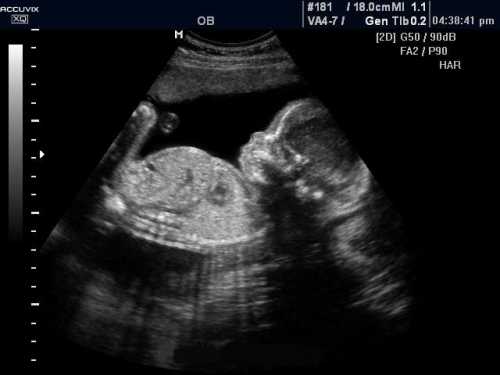

Это результат размягчения связок и суставов в сочетании с повышенной нагрузкой на ноги изза увеличения веса. Вносят свою лепту и отеки. Стопа может прибавить размера, но не стоит переживать после родов она вернется в норму. Если вы еще не прошли второе плановое. УЗИ, на неделе беременности самое время это сделать. Ребенок уже сформирован, похож на полноценного человека, можно разглядеть его лицо, определить пол. На неделе врач назначит вам очередной визит, во время которого оценит ваше самочувствие, течение беременности, при необходимости назначит дополнительные исследования и анализы. Выделите ее и нажмите.